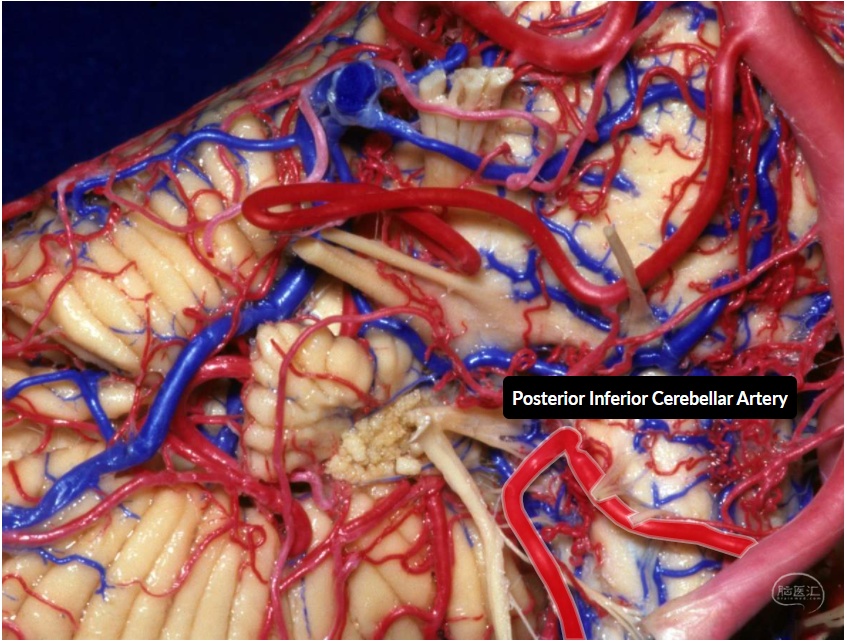

小脑后下动脉(PICA)是最复杂、迂曲的小脑动脉,其行程及供血区域变异较大,与小脑延髓裂、第四脑室顶壁的下半、小脑下脚以及小脑枕下面关系密切。小脑后下动脉是后循环动脉瘤常见发生部位,闭塞后可导致延髓背外侧综合症,准确识别和判断小脑后下动脉在神经血管疾病的诊断与治疗中具有重要价值。

1.小脑后下动脉解剖

图1 小脑后下动脉分段(外侧面观示意图)。小脑后下动脉发自于椎动脉V4段,共分为5段,分别为延髓前段、延髓外侧段、扁桃体延髓段、膜帆扁桃体段和皮层段。延髓前段和延髓外侧段的分界点为橄榄最高点;延髓外侧段和扁桃体延髓段的分界点为舌咽神经、迷走神经和副神经的连线;扁桃体延髓段和膜帆扁桃体段的分界点为脉络带(四脑室下界);膜帆扁桃体段与皮层段的分界为小脑后下动脉离开扁桃体、蚓部和小脑半球之间裂隙处。扁桃体延髓段形成朝向尾部的尾襻,膜帆扁桃体段形成朝向头端的颅襻。皮层段分为内侧干和外侧干,内侧干向小脑蚓部,外侧干供应小脑半球枕下面及小脑扁桃体。

图2 小脑后下动脉后外侧面观。延髓前段、延髓外侧段、扁桃体延髓段发出穿支动脉进入延髓前面、外侧面和后面,这些穿支动脉可在延髓表面与椎动脉V4段发出的穿支动脉形成吻合。扁桃体延髓段和膜帆扁桃体段可发出脉络膜动脉供应四脑室脉络丛。

图3 小脑后下动脉后面观,图中黑箭所示为脉络膜附着于延髓的脉络带,同时也是四脑室的下界,为扁桃体延髓段与膜帆扁桃体段的分界点。膜帆扁桃体段发出脉络膜动脉供应第四脑室顶壁中线及外侧隐窝内侧的脉络丛,颅襻部位可发出分支供应齿状核。小脑前下动脉发出脉络膜动脉供应外侧隐窝外侧的脉络丛,与小脑后下动脉之间可形成吻合。

图4 小脑后下动脉内侧面观。图中黑箭所示为膜帆扁桃体段与皮层段的分界点,即小脑后下动脉离开小脑半球、小脑扁桃体及小脑蚓部之间裂隙处。皮层段分为内侧干和外侧干,内侧干供应小脑蚓部,外侧干供应小脑半球枕下面和小脑扁桃体。

图5 小脑动脉外侧面观。小脑后下动脉、小脑前下动脉及小脑上动脉皮层支之间可形成丰富的吻合。